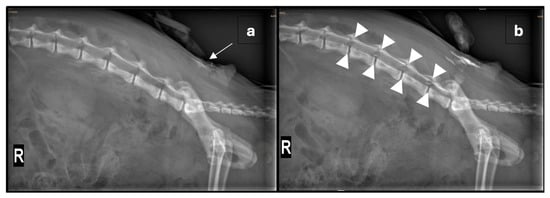

Given the severity of the trauma, an extradural catheter (Perifix® One Paed, 24G, 720 mm, B. Braun Medical AG, Melsungen, Germany) was placed using a Tuohy extradural needle (Perican® 20G, B. Braun Medical AG, Germany) with the patient positioned in sternal recumbency. After aseptic preparation of the lumbosacral region and placement of a sterile drape, the needle was inserted at the lumbosacral junction. The extradural space was identified using the lack-of-resistance technique with saline and air, and an aspiration test was negative. A lateral radiograph was then obtained, and the catheter was advanced 5 cm. Diluted non-ionic iodinated contrast medium (0.5 mL iohexolum (Accupaque, 300 mg/mL, GE Healthcare AG, Opfikon, Switzerland) diluted in 1 mL NaCl 0.9%) was injected through the catheter, initially with a low volume to visualise the catheter’s position (Figure 1a). A repeat radiograph, taken after the entire contrast volume was injected, confirmed extradural placement and appropriate contrast spread (Figure 1b). The catheter was then trimmed to 5 cm from its exit site, and a connector as well as a bacterial filter (Perifix® EF 0.2 µm, B. Braun Medical AG, Germany) were attached. The catheter was primed with 0.5% ropivacaine, and the bacterial filter was secured with sutures cranial to the insertion site. These were then covered with a transparent occlusive bandage (Cosmopor transparent, 9 × 7 cm, Hartmann AG, Heidenheim, Germany) and a purpose-made wound protection body used to cover the surgical wounds, as well as the catheter. Subsequently, 1 mL of 0.5% ropivacaine (0.13 mL/kg) was administered, with repeat injections given at 6 h intervals overnight.

Correct catheter placement is crucial for effective analgesia and can be verified using imaging modalities such as radiography, fluoroscopy, or ultrasonography [3]. Other implications of inappropriate placement include inadvertent dural puncture, catheter coiling, and mechanical or chemical injury of the spinal cord [7]. In this case, contrast radiography was used to verify the catheter’s position. The spread of contrast from L3/4 to L7/S1 was observed, suggesting appropriate distribution of the local anaesthetic, although the catheter tip was not directly visualised. A larger volume of undiluted contrast could have enhanced visualisation, but in the authors’ experience, undiluted viscous contrast risks blockage of narrow lumened catheters. On the second day, catheter placement was verified using the injection of a fast-acting local anaesthetic, lidocaine, testing spinal reflexes and sensitivity pre- and post-injection. Aside from correct catheter positioning, the risk of kinking or breakage should be carefully monitored and minimized [7]. At the time of catheter removal, the insertion site appeared unremarkable, and the catheter was intact without any signs of mechanical failure.

Figure 1. (a) Right lateral radiograph of the vertebral column and pelvis showing the positioning of the extradural catheter (arrow) after the injection of a small amount of radio-opaque dye. (b) Repeated right lateral radiograph after the administration of 0.5 mL non-ionic iodinated contrast media, diluted in 1 mL NaCl 0.9% solution, through the extradural catheter. The tip of the extradural catheter is not clearly identified; however, by comparing the pre- and post-contrast images, a mild amount of radiopaque material is seen reaching the L3-4 neuroforamina (outlined by arrowheads). Within the abdomen, there is diffuse heterogeneous loss of serosal detail and multifocal areas of free gas following exploratory laparotomy.